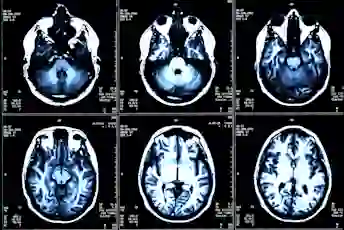

从您的MRI中有意义

这是这些年度灰度脑扫描对您的疾病进展的说法。